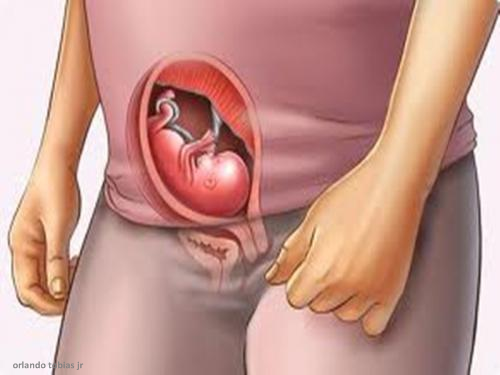

Sua 14a semana começa 1-3 semanas de gravidez 4 semanas de... Continuar Lendo

Sua 16a semana começa 1-3 semanas de gravidez 4 semanas de... Continuar Lendo

Sua 15a semana começa 1-3 semanas de gravidez 4 semanas de... Continuar Lendo

Sua 13a semana começa 1-3 semanas de gravidez 4 semanas de... Continuar Lendo